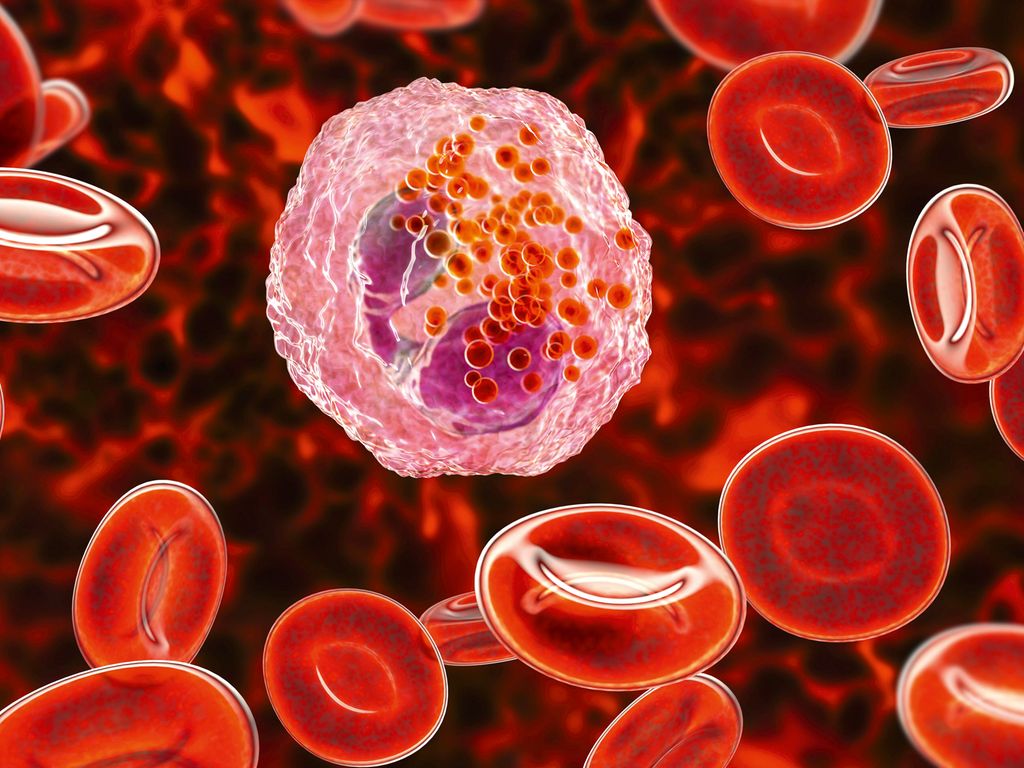

Multiples Myelom: Diagnostik, Erstlinientherapie und Therapie des ersten Rezidivs

Hämatologie | Innere Medizin | Onkologie

| gültig bis Februar 2027

Hämatologie | Innere Medizin | Onkologie